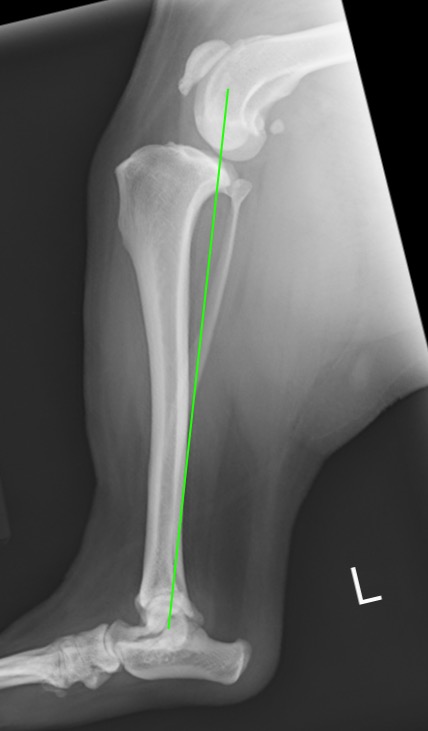

正常な足。大腿骨と脛骨の機能軸が直線状に並んでいる。